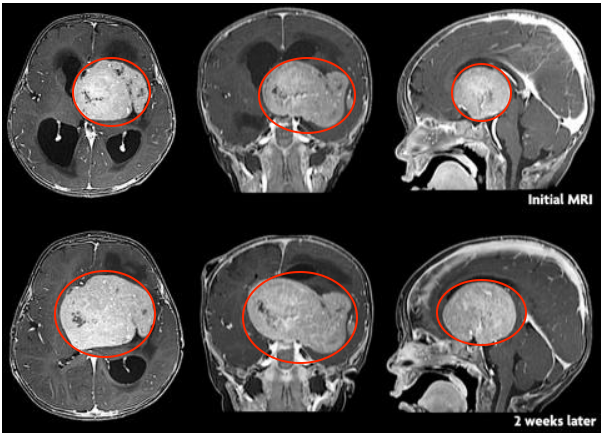

在开头的男孩中,短短两周内,他的脑膜瘤就几乎充斥了整个大脑,于是很多人不禁要问,为何他的脑膜瘤生长得如此之快?

事实上,不同级别的脑膜瘤生长速度有所区别,I级肿瘤生长缓慢,也常见于成年人,而II级肿瘤则生长较快,组织和细胞异常增多,常被称为非典型性脑膜瘤,占脑膜瘤病例的18%。这些肿瘤生长速度比良性脑膜瘤快,常以侵犯正常脑组织为特征。

此外,III级肿瘤的生长和扩散则更快,常被称为间变性或恶性脑膜瘤,其细胞异常增多,生长速度、对大脑的侵犯程度以及复发几率都是高于良性和非典型脑膜瘤的。